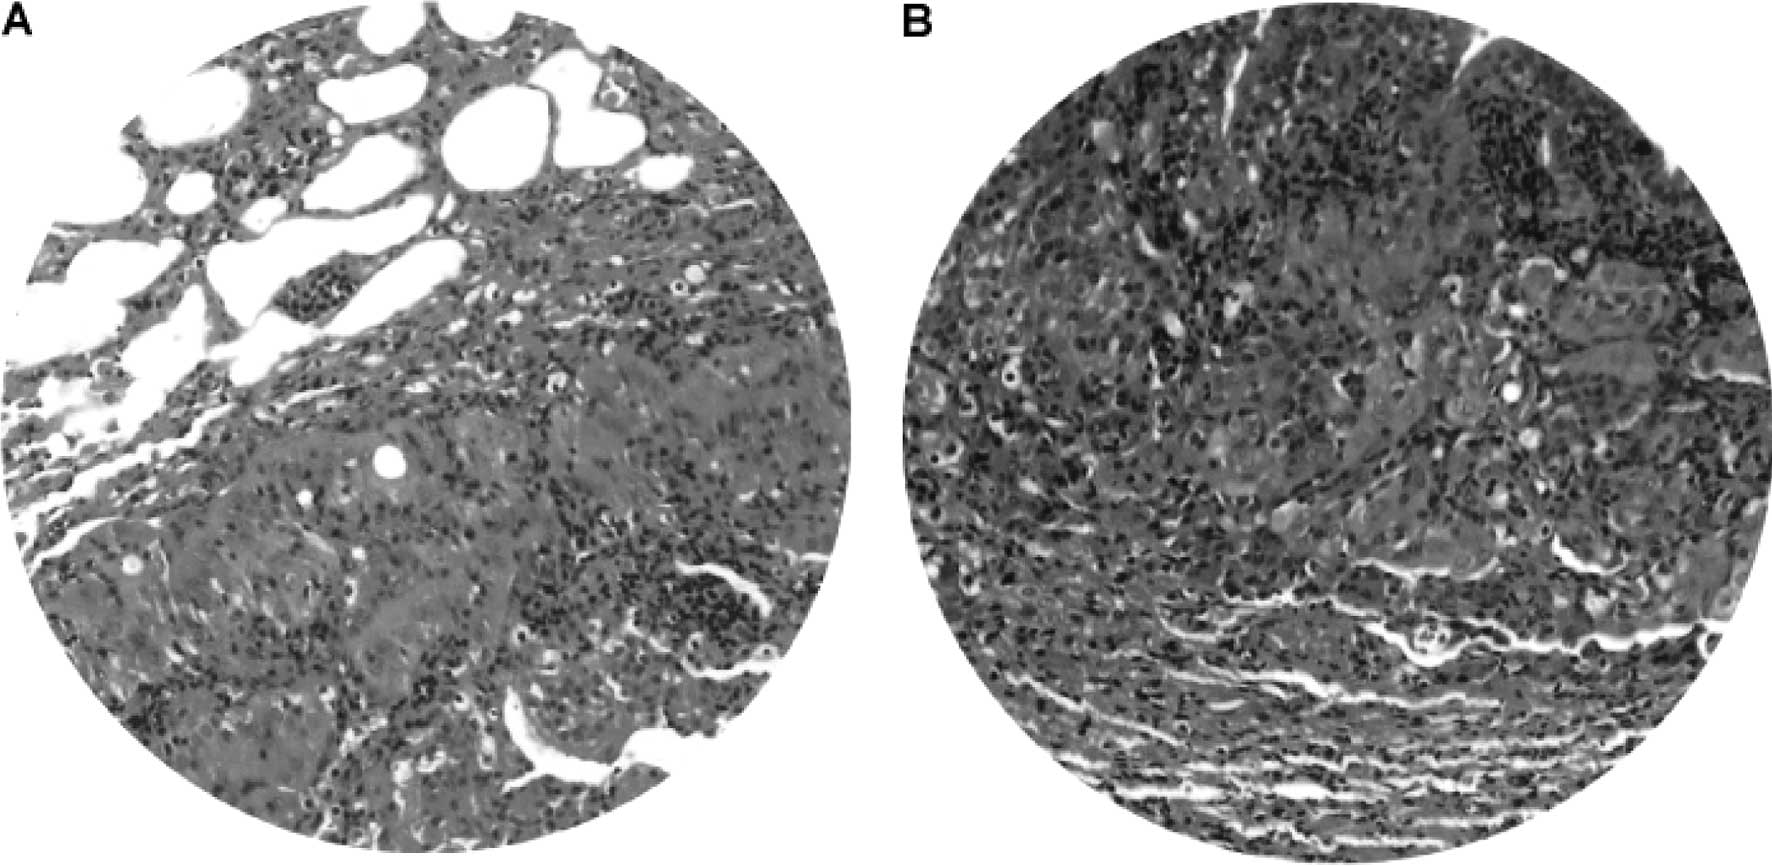

No tumors were observed in the control animals. The gross pathological findings of DEN-treated livers included ascites, hepatomegaly, small hepatic cysts and multiple hepatic nodules. Gross examination at 45 and 50 weeks of the DEN treatment demonstrated macronodular HCC in 33.3% (4/12) of the DEN-treated Syrian hamsters (Fig. 2). The livers with HCC were enlarged with multiple small nodules of 0.2–0.5 cm in diameter (Fig. 2A–D), or with a single large nodule of 3 cm in diameter (Fig. 2E). Light microscopy and H&E staining showed nodular HCC (Fig. 3A). There were frequent bizarre neoplastic cells and abnormal mitotic figures (Fig. 3B). In addition, the HCC nodules were accompanied by chronic inflammatory infiltrates (Fig. 3A) and separated by cords of atrophic hepatocytes (Fig. 3A).

Figure 3.

Light microscopy of macronodular hepatocellular carcinoma. (A) H&E staining demonstrates the nodular appearance of HCC with frequent bizarre cells and mitotic figures (A and B, arrows). The tumor nodules are accompanied by chronic inflammatory infiltrates (dashed circle) and separated by cords of condensed residual hepatocytes (*). cv, central vein. Original magnification: A, x200; B, x400.

Gross and microscopic examination revealed lung tumors in 2/4 hamsters at 25–50 weeks of the DEN treatment. The lung tumor mass was most frequently single rather than multiple, and varied from 0.3 to 1.2 cm in diameter. Light microscopy and H&E staining demonstrated well-differentiated neoplastic cells (Fig. 11A) admixed with chronic inflammatory cell infiltrates (Fig. 11B). The morphology of the neoplastic cells in the lung was different compared to that of HCC. Consistently, immunohistochemistry illustrated that only a few macrophages, but not the neoplastic cells, were positive for AFP (Fig. 12), indicating that the lung tumors may not be HCC metastasis. No tumors were detected in the kidney, pancreas, spleen or other anatomical sites.

Figure 11.

Lung tumor. Light microscopy and H&E staining demonstrated (A) well-differentiated neoplastic cells admixed with (B) chronic inflammatory infiltrates in lung tumors. Original magnification, x200.